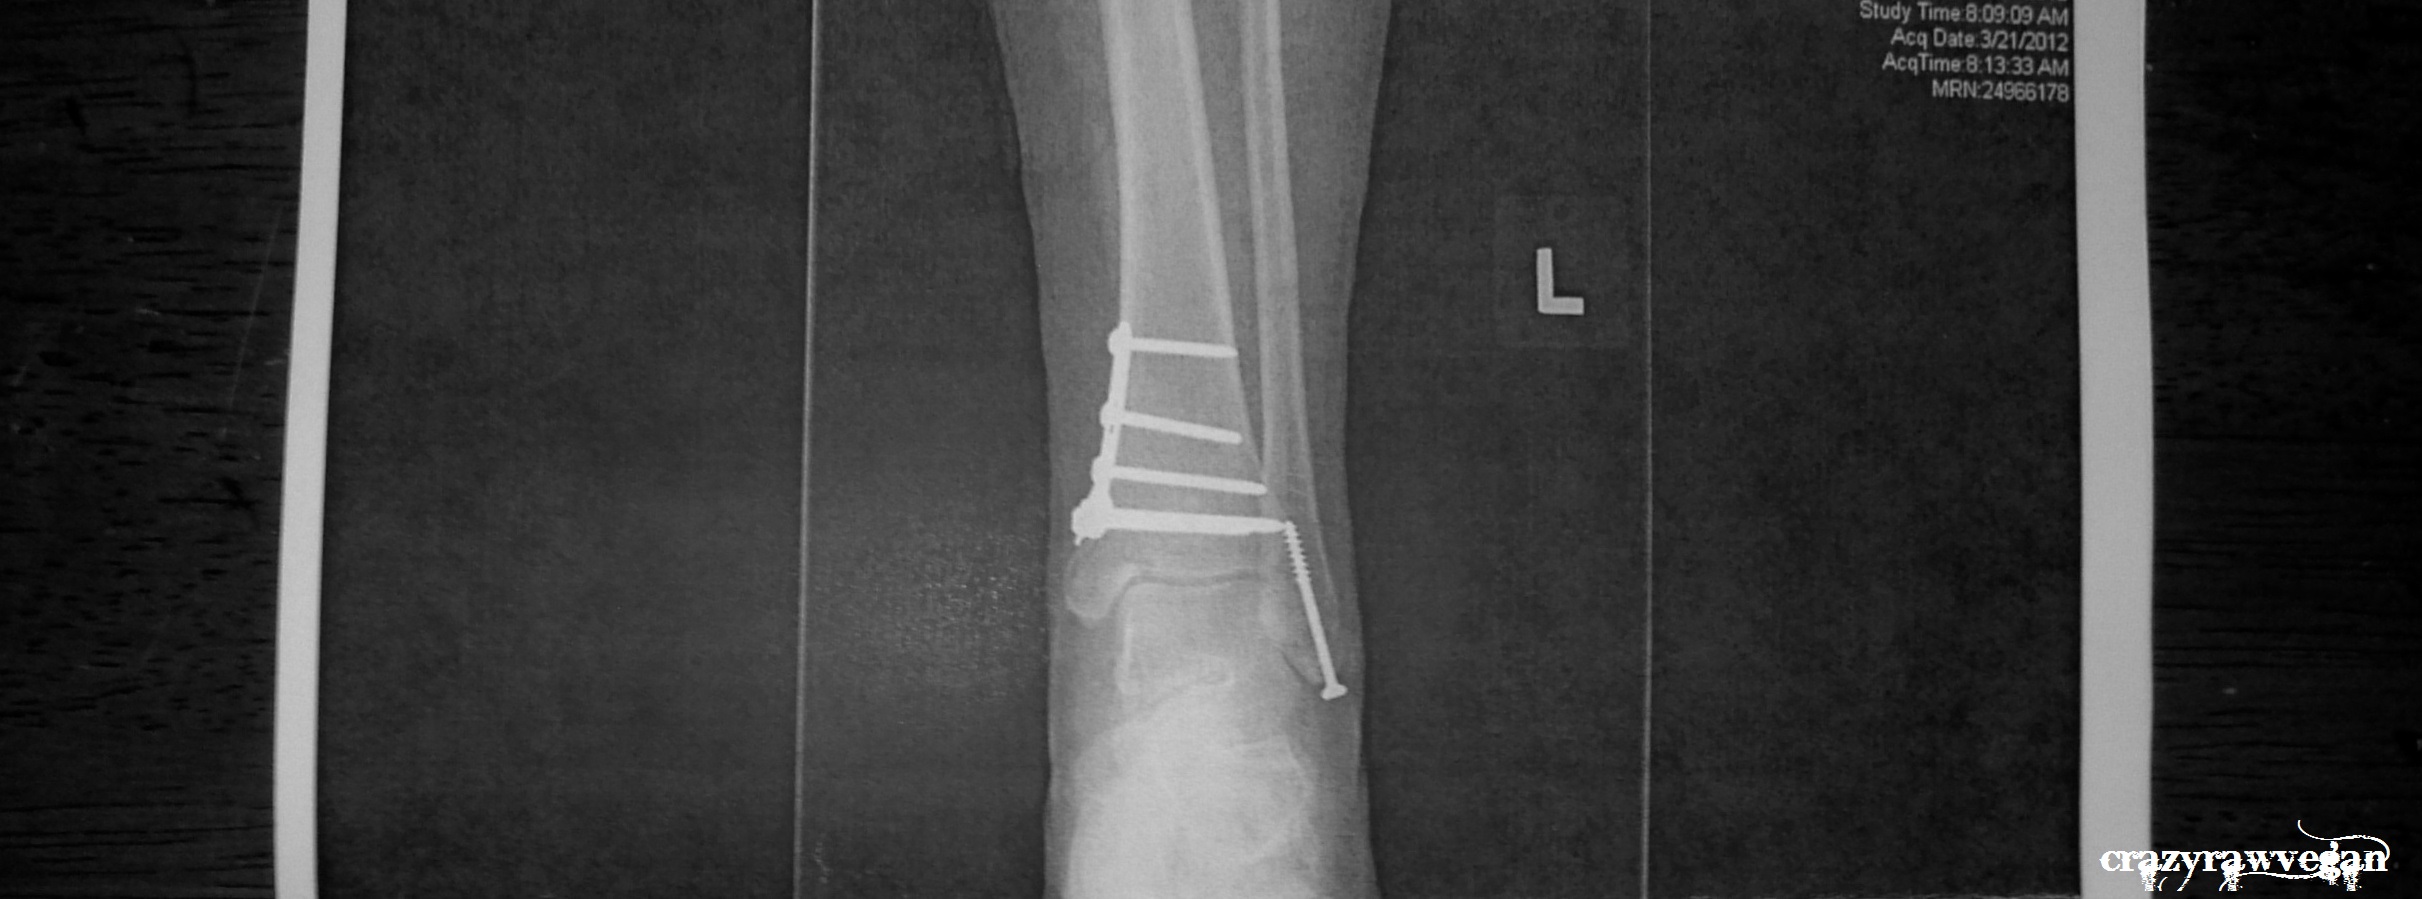

Boston Half Marathon in October.

Why running? Well, I suppose I had my ‘great adversity’ last year when I was in a wheelchair after a snowboarding accident. One broken ankle and one so badly sprained I couldn’t walk on it for weeks. Contusion in my femur, a damaged MCL from the previous ski season. I was scooching around the house on my bum (and a skateboard), leveraging myself onto the toilet with my cast on the bath edge, being carried down the stairs… then I was in two air casts and crutches for months. So I’m running to maintain the feeling of gratitude for my body I felt when I got back on my feet and was told everything had healed ‘perfectly’, and I’m running for those people who lost their limbs in the marathon bombing. Not because I can pretend to understand the permanency, but because I have a tiny inkling of the challenges that presents.